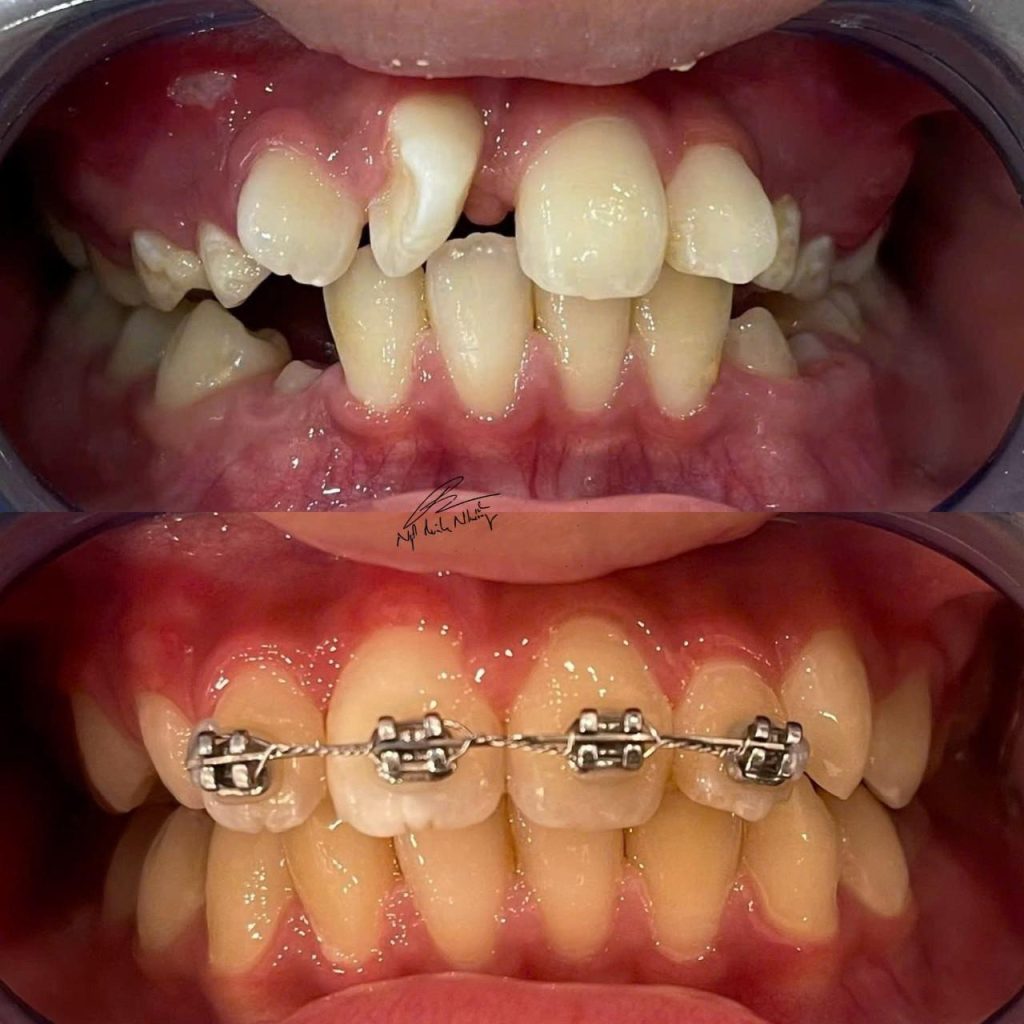

- Phát hiện và điều chỉnh các vấn đề phát triển hàm : Niềng răng sớm, thường từ 6 đến 8 tuổi, giúp bác sĩ chỉnh nha phát hiện và can thiệp kịp thời các vấn đề về sự phát triển của hàm và răng. Việc điều chỉnh sớm có thể giúp tránh các vấn đề nghiêm trọng hơn trong tương lai, như lệch lạc răng miệng, sai khớp cắn, hoặc các vấn đề về chức năng nhai.

- Điều chỉnh sự phát triển của xương hàm : Vào giai đoạn trẻ em đang trong quá trình phát triển, các xương hàm vẫn còn dẻo dai và có thể điều chỉnh dễ dàng hơn. Niềng răng sớm giúp tác động vào sự phát triển của hàm, giúp cho hàm trên và hàm dưới phát triển hài hòa, tránh tình trạng răng mọc lệch, vẩu hay móm sau này.

- Giúp răng mọc đúng vị trí : Khi niềng răng sớm, bác sĩ có thể tạo không gian cho các răng vĩnh viễn mọc đúng vị trí, giúp tránh việc phải nhổ răng vĩnh viễn sau này nếu răng mọc chen chúc quá nhiều.

- Cải thiện thẩm mỹ và tự tin : Niềng răng sớm cũng giúp cải thiện thẩm mỹ khuôn mặt của trẻ, đặc biệt trong các trường hợp có vấn đề về răng vẩu hoặc móm. Điều này có thể giúp trẻ tự tin hơn khi giao tiếp và hạn chế các vấn đề tâm lý liên quan đến ngoại hình.